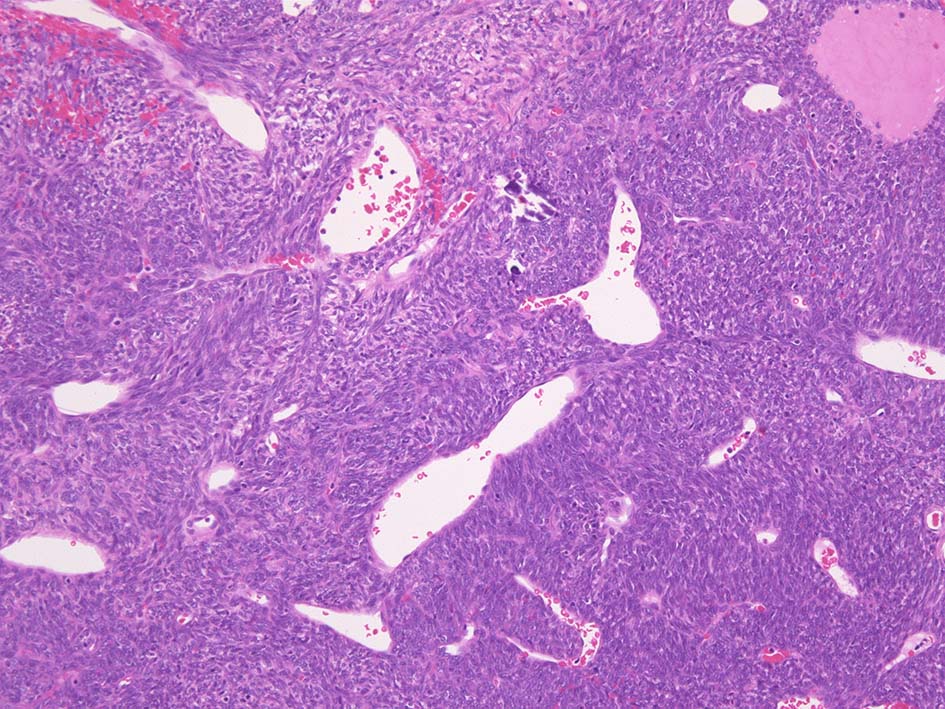

滑膜肉腫の最大の特徴は類上皮肉腫とならび代表的な上皮様分化を示す組織像にある。

腫瘍細胞の上皮的性格については電顕で上皮成分に基底膜形成や接着斑がみられること, 免疫染色で種々の分子量のcytokeratinやEMAの発現が認められることより真の上皮への分化と考えられている*18

1. biphagic type; 古典的なタイプでさまざまな割合で明らかな上皮成分と紡錘細胞が混在する。

2. monophagic fibrous type; 線維肉腫様の紡錘細胞のみが増殖し上皮様細胞はみられない。